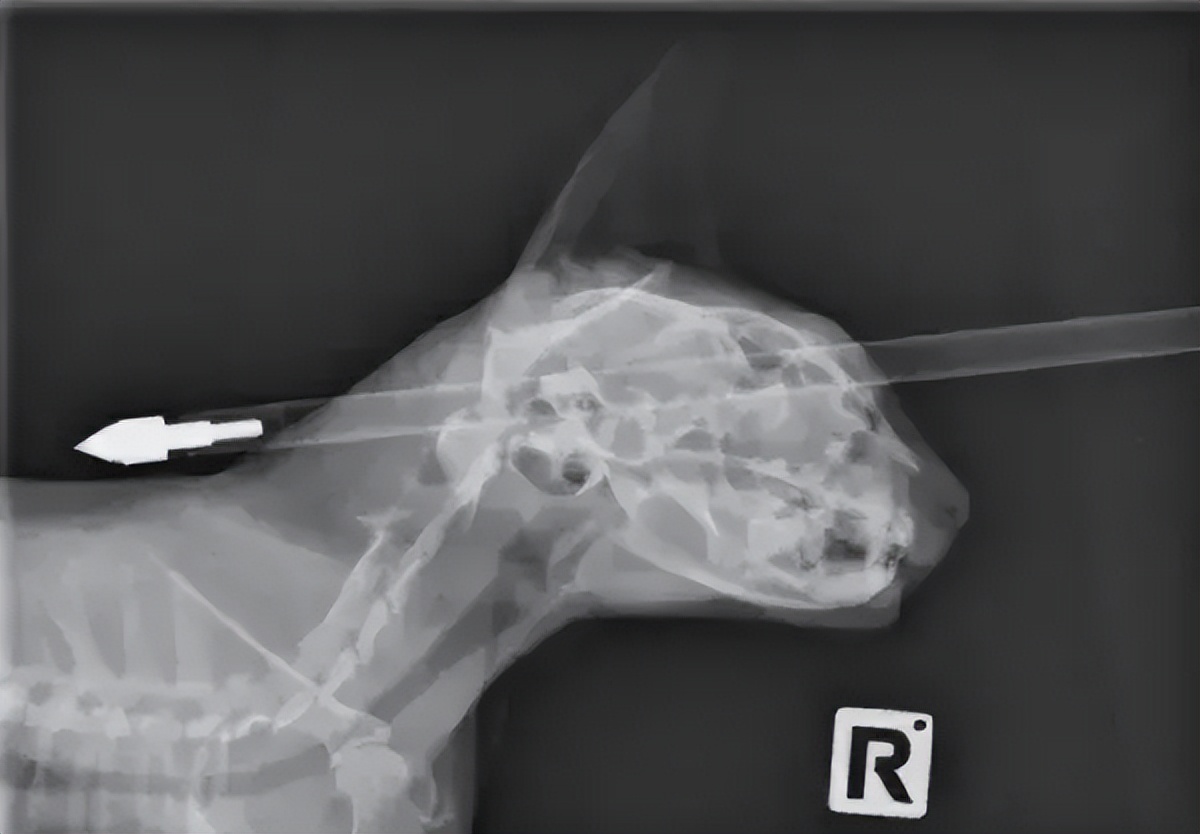

这只猫还是真挺坚强的啊,脑门被穿了这么大一个窟窿都没事,现代版猫坚强啊!希望能挺过这次劫难吧,每个生命都值得敬畏!